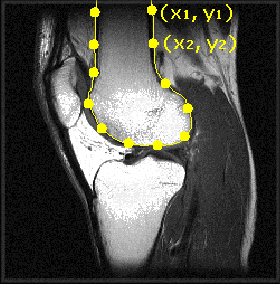

Figure: Landmark identification and mark-up in medical images

We now have our set of shapes in a common representation. However, we first have to remove the degrees of freedom corresponding to position, orientation, and scale, as mentioned above. The method most commonly used is Procrustes analysis. The generalised Procrustes procedure was developed in 1991. Procrustes analysis translates, rotates and scales each shape, so as to minimise the sum of squared distances between corresponding landmarks. Having aligned all the shapes, the mean shape is then obtained by simply averaging the position of each corresponding landmark across the whole set of shapes.